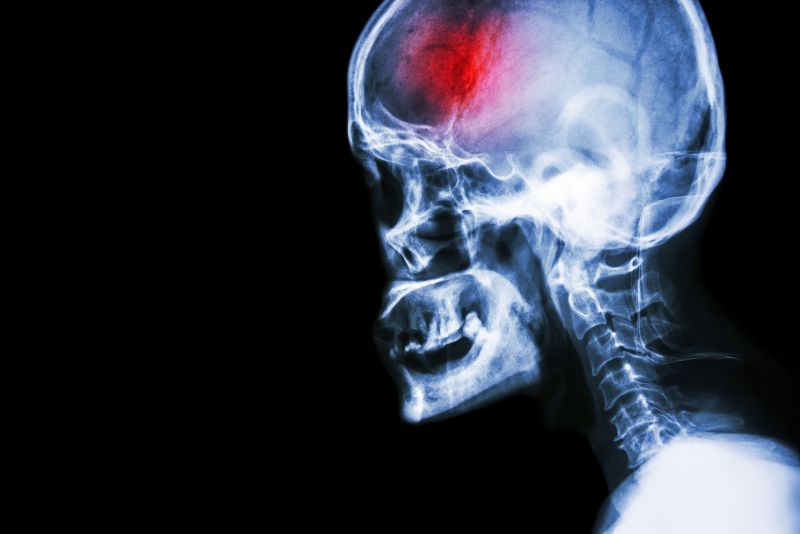

A stroke (previously known as a cerebrovascular accident) when there is a decreased flow of blood to the brain from either a blockage in the blood vessels that supply the brain (ischemic stroke), or a bleed from the blood vessels that supply the brain (hemorrhagic stroke). When the blood flow to the brain is blocked it prevents the brain from getting the needed oxygen and nutrients to function. Without oxygen the brain cells can be permanently damaged or die and the physical and mental functions related to that area of the brain will be affected. A stroke is a medical emergency and rapid treatment is crucial to decreasing the damage caused by a stroke.

- Ischemic stroke: a stroke that is caused by a blockage (clot) that disturbs the blood flow to the brain.

- Hemorrhagic stroke: a stroke that is caused by a bleed that disturbs the blood flow to the brain and puts pressure on the surrounding tissue.